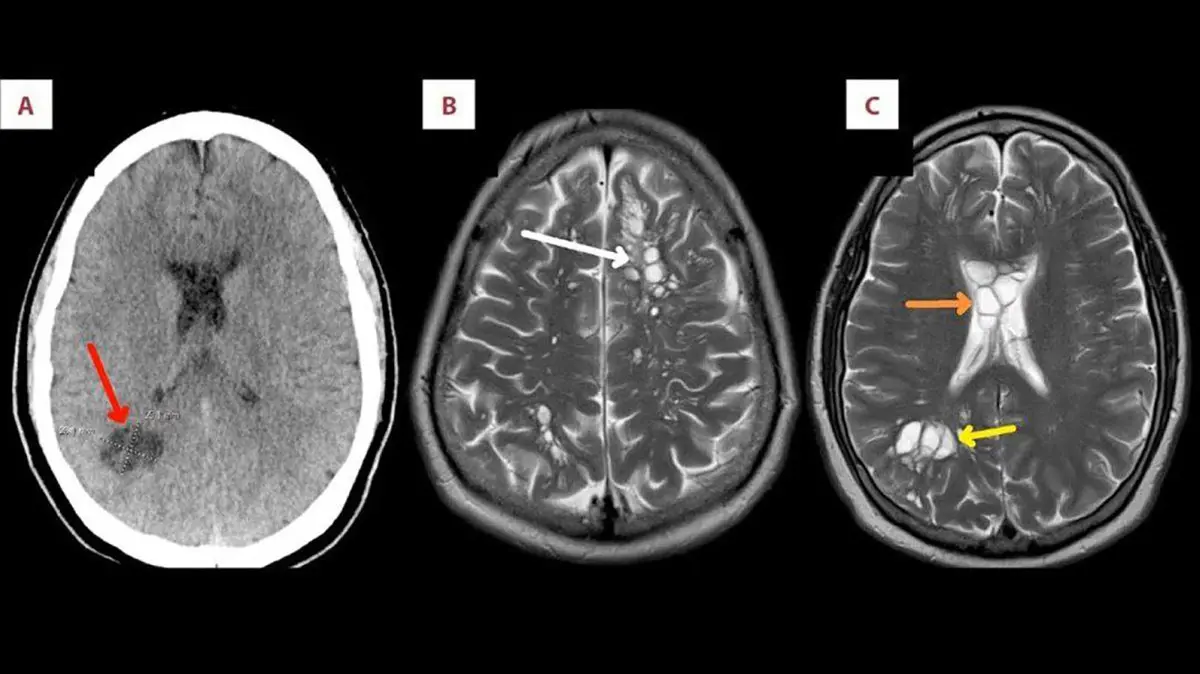

به گزارش رکنا، اسکن مغزی و ام آر آی ، کیستهای متعدد در هر دو نیمکره مغز بیمار و همچنین تورم مغزی را نشان دادند و متخصصان بیماریهای عفونی تأیید کردند که دلیلش کرم نواری گوشت خوک است که در مغزش تخم گذاشته و بافت زیر جمجمهاش را تحریک میکند.

سی تی اسکن و ام آر آی کیست های متعدد را در دو طرف مغز او نشان داد. تشخیص پزشکان عفونت انگلی نوروسیستیسرکوزیس بود که بر اساس آن، کیستهای لارو - کیسههای محصور حاوی مرحله نابالغ یک انگل - کرم نواری گوشت خوک قسمتهای مختلف بدن را آلوده کرده و باعث التهاب میشوند.